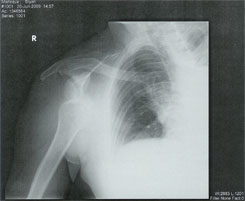

We've had a bit of a schedule change lately and have had to temporarily put on hold some possible mission trips, because of a recent mishap: Surfing is much easier on the body when you fall than its poor red-headed step child skateboarding; cement is merciless. After a string of injuries back in the day I hung up the skateboard until Patrick got into it recently. One little rock can ruin your day though, I hit one just cruising and going straight doing basically nothing. You'd think it would have happened while I was hitting vertical in the pool right before this at the skate park we were at, it started to feel like the old days, but then... That little pebble catapulted me like a crash-test dummy straight into a dislocated shoulder, the real problem was the way I landed with my arm up in the air, usually I'm ready to tuck and roll, it's when your guard is down that you get broadsided. The doc at the emergency room, where I spent 6 long fun-filled hours, said it's one of the most painful injuries there is; pure agony is how I'd put it. After being shot up like a pin cushion with numerous painkillers, they finally had to knock me out to reset it. Now it's ice, rest, then rehab. Keep us in your prayers for a full and speedy recovery without complications and consider us in your giving as we've got lot's of extra expenses with deductibles and co-pays to pay off due to limited insurance.

One little rock can ruin your day when skateboarding. Launched straight into the ER by a shoulder dislocation, I had to be completely knocked out to reset it. After waiting and waiting in severe pain they finally got around to it--they had to, of course, give medicine to people for things like a common cold first--I eventually got discharged after 6 fun-filled hours. Praise God for the young Hispanic guy I'd never met before, who so kindly drove me all over town looking for an open medical facility as I moaned and groaned in agony. He told Patrick: "Keep your hand on your dad and don't stop praying!" while he fought traffic looking for a medical facility.